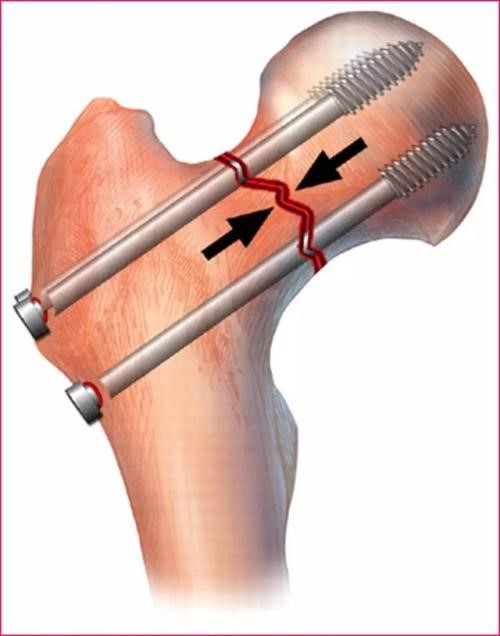

三、股骨粗隆间骨折

保守治疗风险大,极可能引发一系列并发症,如骨折移位、褥疮、肺炎、下肢血栓等,建议行手术复位内固定治疗,手术后尽早减轻疼痛,早期进行功能锻炼,避免长期卧床。并发症如下图: